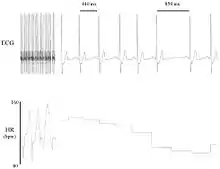

Heart rate variability (HRV) is the physiological phenomenon of variation in the time interval between heartbeats. It is measured by the variation in the beat-to-beat interval.

Other terms used include: "cycle length variability", "RR variability" (where R is a point corresponding to the peak of the QRS complex of the ECG wave; and RR is the interval between successive Rs), and "heart period variability".

Methods used to detect beats include: ECG, blood pressure, ballistocardiograms,[1][2] and the pulse wave signal derived from a photoplethysmograph (PPG). ECG is considered superior because it provides a clear waveform, which makes it easier to exclude heartbeats not originating in the sinoatrial node. The term "NN" is used in place of RR to emphasize the fact that the processed beats are "normal" beats.